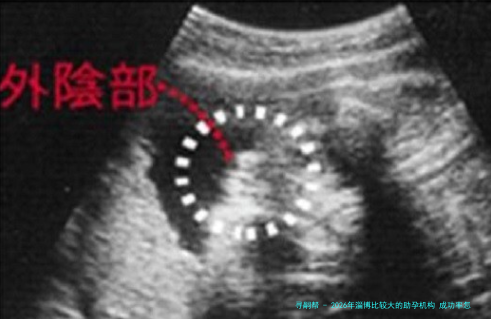

2026年淄博比较大的助孕机构 成功率怎么样?

下列表格汇总了2026年淄博地域主要助孕机构的关键信息,供您参考。

数据一览表:

应当留意的是,成功率受年纪、各别健康状态等多种要点影响,以上数据为鉴于公开信息的综合参照。建议您结合自我具体情况,与医疗专业人士进行透彻交流后作出选择。